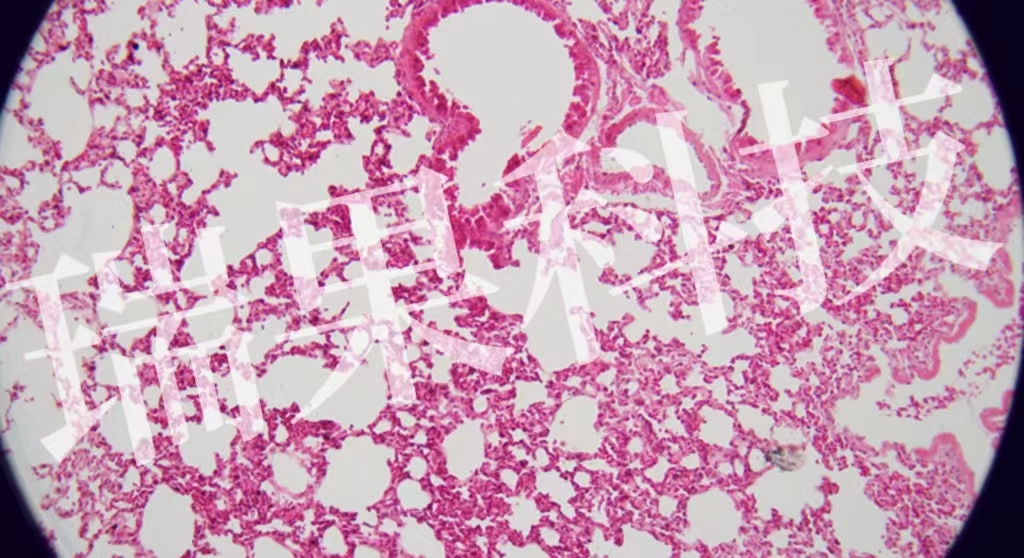

HE染色:苏木精 - 伊红染色法 ( hematoxylin-eosin staining ) ,简称HE染色法 ,石蜡切片技术里常用的染色法之一 。苏木精染液为碱性 ,主要使细胞核内的染色质与胞质内的核酸着紫蓝色 ;伊红为酸性染料 ,主要使细

HE染色:苏木精 - 伊红染色法 ( hematoxylin-eosin staining ) ,简称HE染色法 ,石蜡切片技术里常用的染色法之一 。染液为碱性 ,主要使细胞核内的染色质与胞质内的核酸着紫蓝色 ;伊红为酸性染料 ,主要使细胞质和中的成分着红色 。HE染色法是组织学、、病理学教学与科研中最基本、使用最广泛的技术方法。

肺2-1-20x